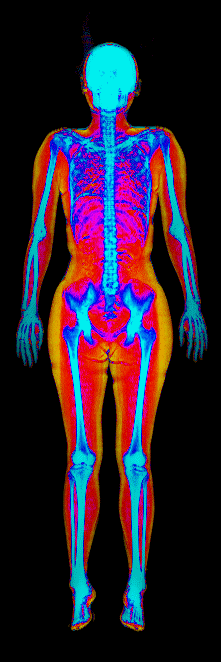

This page features real, anonymized DEXA scan images from BodyStats clients, organized by gender and body fat percentage in 5% increments. DEXA (Dual-Energy X-ray Absorptiometry) is the clinical gold standard for measuring body composition — far more accurate than scales, calipers, or visual estimates.

Each colorized scan shows the distribution of fat tissue (shown in warmer colors) and lean tissue (cooler colors) throughout the body. Compare your own DEXA scan to others in your range, or see what different body fat levels actually look like on a scan.

Female DEXA Scans by Body Fat %

15 to 20% body fat